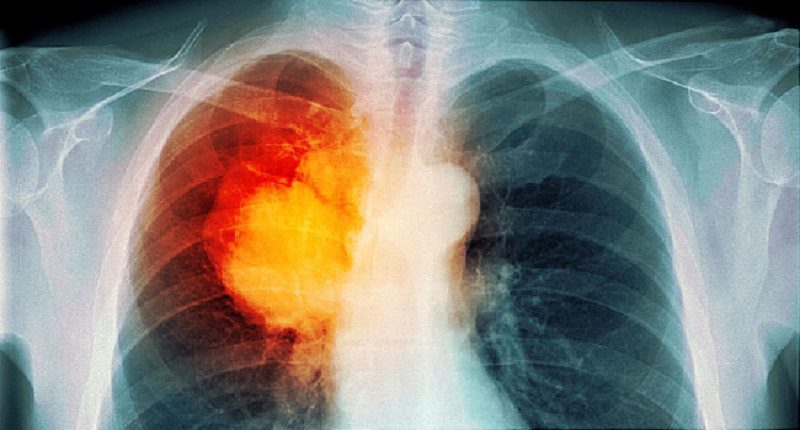

Dünya genelinde her sene 2 milyon civarında kişiye akciğer kanseri teşhisi konmakta ve her sene 1,8 milyon civarında kişide akciğer kanserinden dolayı yaşamını yitirmektedir. Ülkemizde ise her sene 35 bin civarında kişiye akciğer kanseri teşhisi konulmaktadır. Ülkemiz akciğer kanseri tanısında dünyada 9’uncu sırada yer alırken, erkeklere akciğer kanseri tanısı konmasında ise 3’üncü sırada yer almaktadır.

Akciğer kanserinin en önemli nedeni tütün ve tütün mamullerinin kullanılmasıdır. Bunun yanı sıra Covid-19 virüsü salgını da akciğer kanserinin erken tanısında çok büyük bir risk oluşturmaktadır. Çünkü virüs enfekte olacağı korkusuyla hastaneye gidemeyen insanlar, akciğer kanserinde erken tanı şansını kaçırmaktadır.

Akciğer kanserine erken evrede tanı konulduğu zaman cerrahi tekniklerle tedavisinin mümkün olduğuna ve hayatta kalma süresinin uzadığına değinen Prof. Dr. Pınar Çelik, “Ancak Covid-19 virüsünün kendilerine enfekte olmasından korkan hastalar, hemen hastaneye başvurmuyorlar. Sağlık durumları iyice kötüleştiği zaman hastaneye başvuru yapan hastalara yapılan tetkiklerde ise akciğer kanserinin ileri evresinde tanı konulmaktadır. Son dönemde bu durumda olan akciğer kanseri hastalarına sık rastlıyoruz.” dedi.